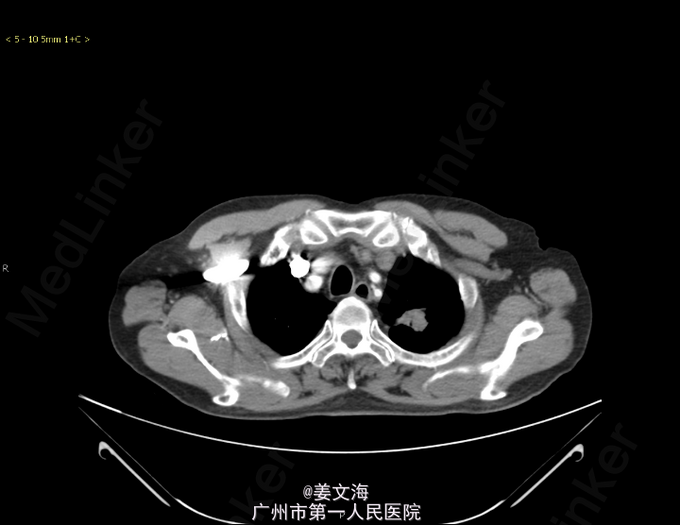

主诉:咳嗽8月余,咳血丝痰6月 病史:患者于8月前因反复咳嗽、咯血就诊于当地医院,当时胸部CT示双肺结核,左上肺真菌感染,痰结核菌培养阳性,予3HRZE/9HR方案抗结核治疗,并予伏立康唑抗真菌治疗。患者因经济原因使用伏立康唑1月后自行停药。后曾短期口服伊曲康唑胶囊。经治疗后,咳嗽减轻,仍间断咯血痰。既往史:高血压病。2007年曾患左肺结核,抗结核治疗1年。现为求进一步诊治来我院。

查体:双肺呼吸音清,未闻及干湿啰音。其余无特殊。 辅助检查: 胸部CT提示:左肺继发型肺结核并空洞形成,考虑合并真菌感染可能性大。右肺多发小结节,考虑结核增殖灶可能。 经皮肺活检病理提示:(左上肺)符合真菌感染。送检物为少量真菌菌丝,呈团状,其形态学符合曲菌。

诊断:1.左上肺真菌感染;2.双肺继发性肺结核;3.高血压病。 处理:予抗结核、先后予伊曲康唑、卡泊芬净针抗真菌、祛痰止咳、止血、降压、对症支持治疗。

随访:经抗真菌和抗结核治疗后,病情稳定,患者咳嗽咳痰症状较前好转,予停用卡泊芬净,改用伊曲康唑口服液(斯皮仁诺)(进) 20ml 口服 bid 带药出院继续口服,继续抗结核治疗。 讨论:肺曲霉菌感染患者的临床表现缺乏特征性,患者多有肺结核等基础疾病,而肺曲霉菌感染症状往往被基础疾病掩盖,极易被忽视。当前肺曲霉菌的主要诊断方法是患者的临床症状,术后病理检查、真菌学检查,影像学检查等。